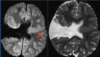

A

Cisto epidermóide

Hipersinal na difusão

Sinal heterogêneo no FLAIR

Extra-axial

19

Cisto epidermóide do SNC

Sinal heterogêneo no FLAIR e Hipersinal na DWI

Extra-axial nas sisternas da base.